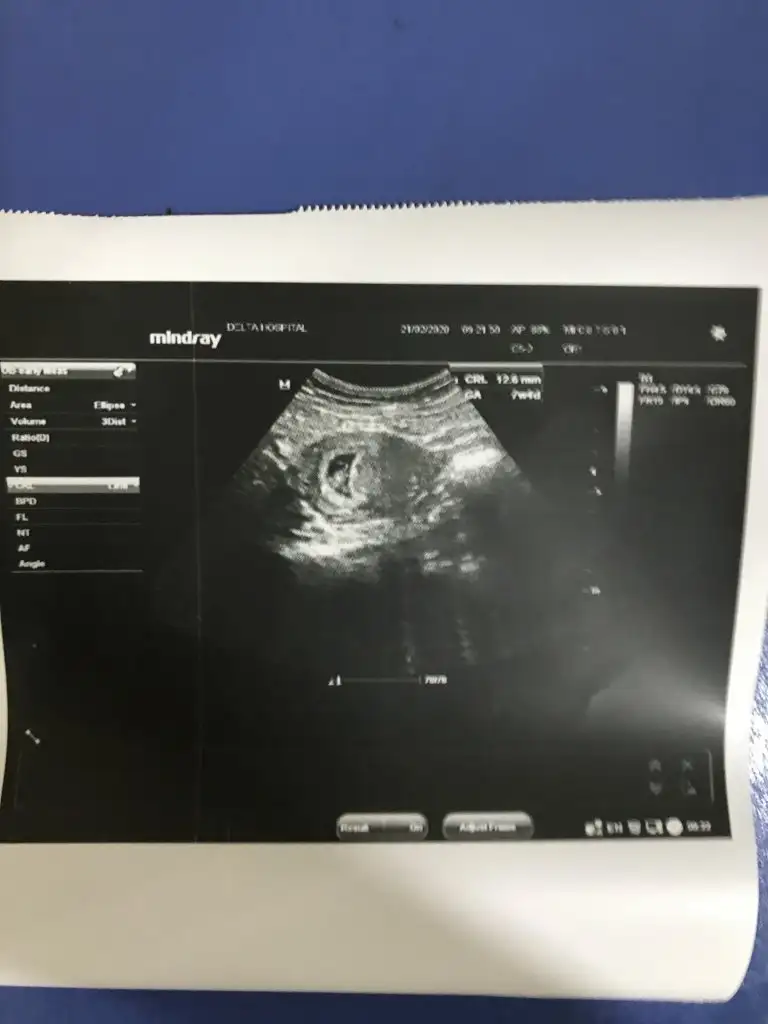

Merhaba. 6 haftalık karından ultrason fotoğrafı bu tahmini olan varmı?

Eklentiler

• 20200115_104527-1-1.webp

20200115_104527-1-1.webp

19,6 KB · Görüntüleme: 110